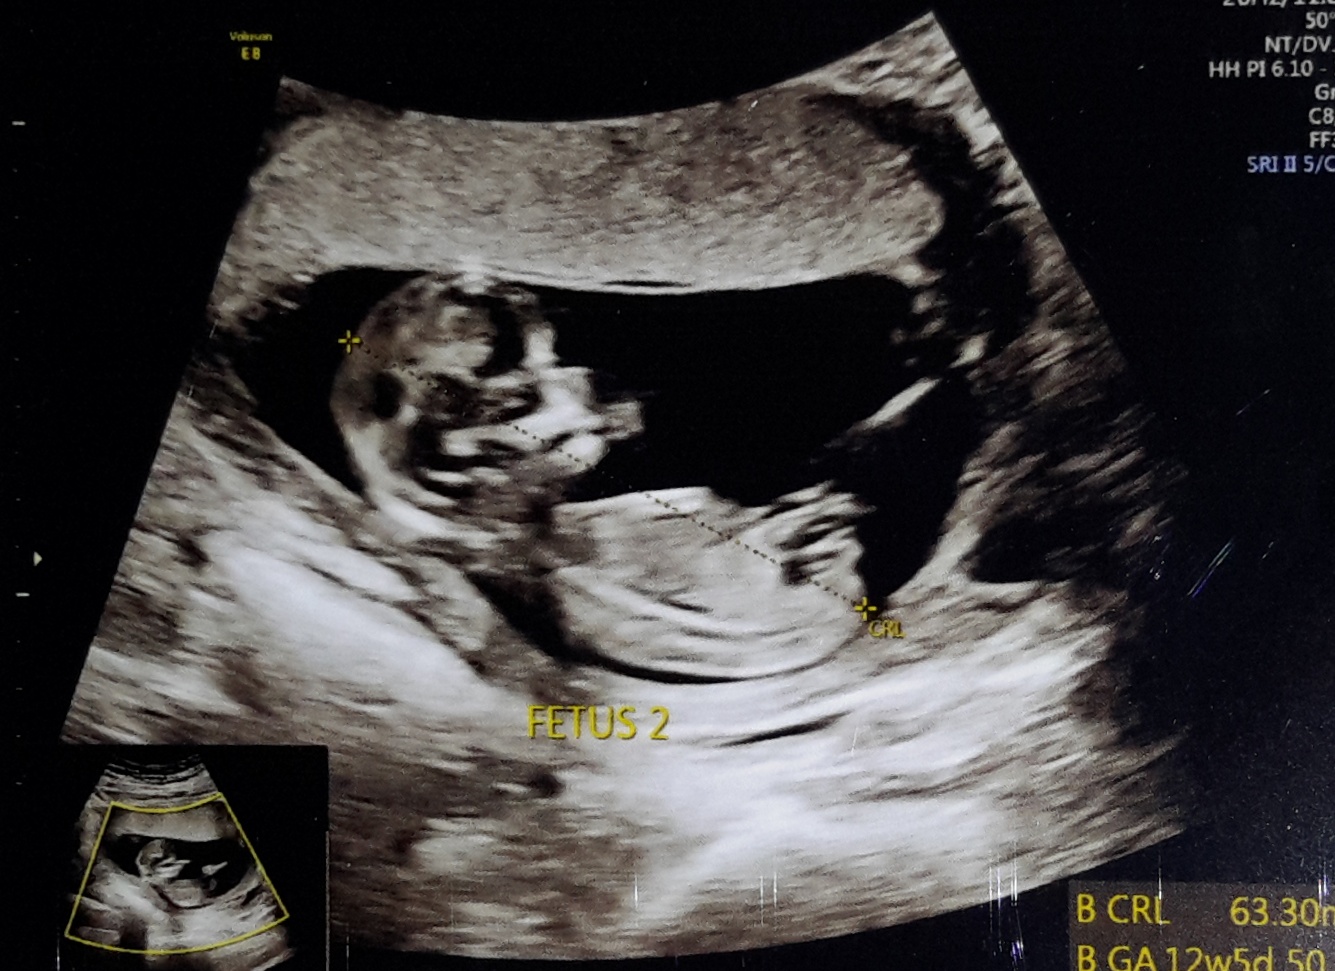

Here we go. 12 weeks ultrasounds

Attachment 40167

Attachment 40168

No nub on baby #1's pic but for baby #2 I see a bit of the nub. Maybe boy? It's so hard to tell as baby is curled up and the nub looks a bit cut off at the end.